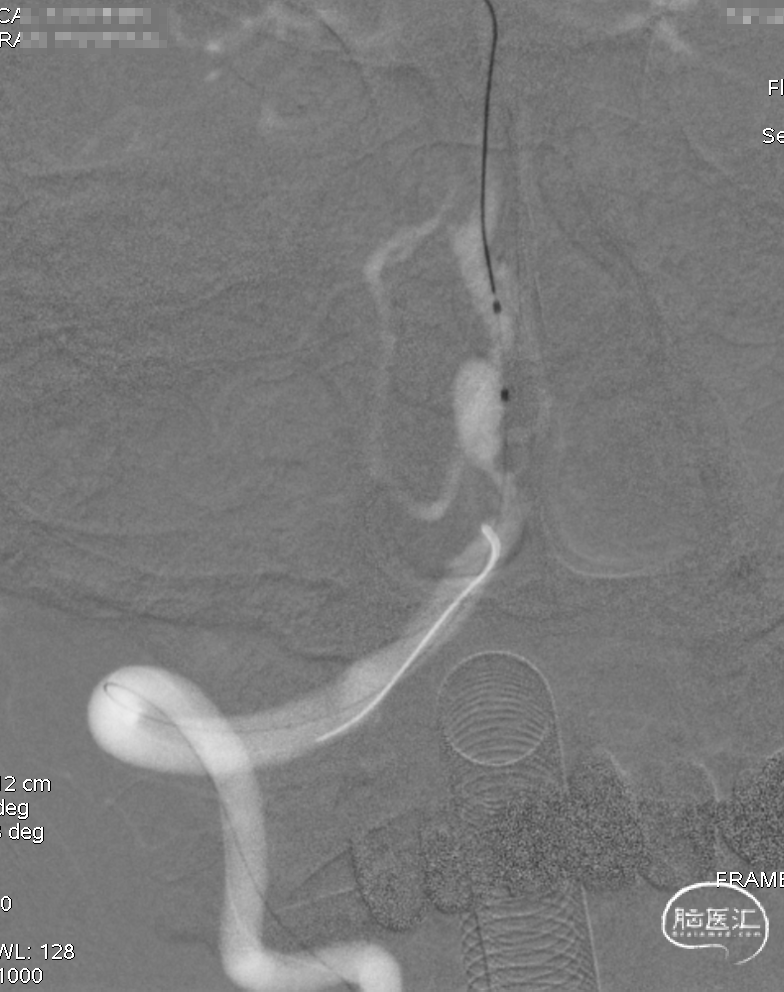

逐步释放Pipeline(3.00*30)。

支架完全释放,微导丝“按摩”支架。